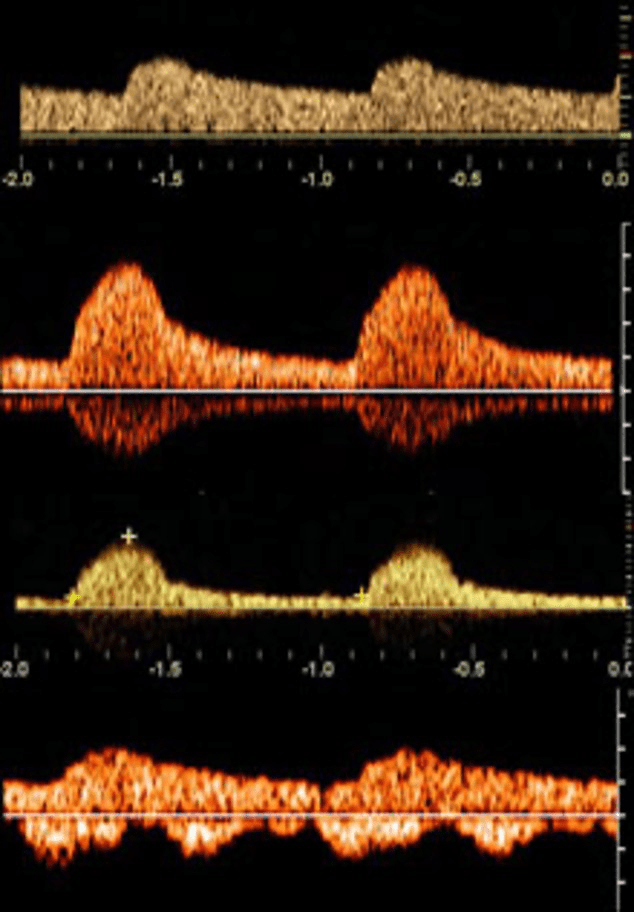

Determine whether this flow pattern is normal or abnormal

What is Abnormal?